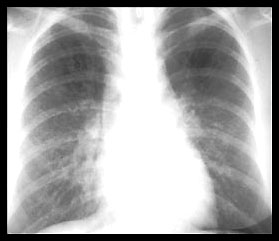

Chest X-ray showing clear lung parenchyma, no | Download Scientific Diagram

Chest X-ray showing clear lung parenchyma, no | Download Scientific Diagram from www.researchgate.net